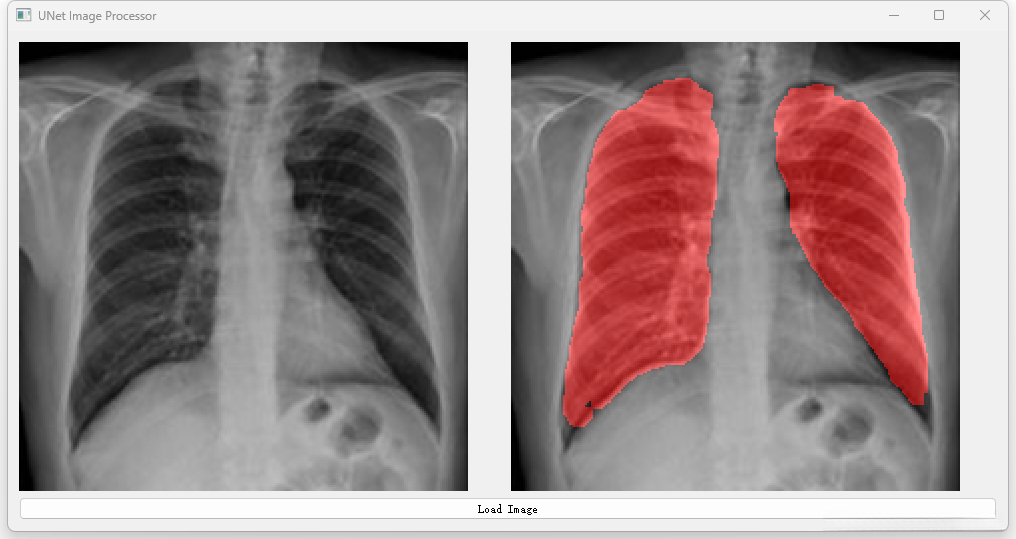

开发一种高效且可靠的U-Net网络架构以解决肺部CT图像分割任务。 通过优化算法设计提升图像分割精度的同时有效抑制噪声污染和伪影生成。 实现对肺部各区域(如支气管血管网等)的精细解析确保诊断准确性。 设计一个操作便捷的人机交互界面便于临床医师进行影像分析及评估。

将经过优化的Unet架构应用于实际临床CT扫描数据中进行分割操作,并实现精准识别目标区域边界的目标达成。

对分割结果实施后端质量控制流程:包括噪声去除、空洞填充等步骤确保最终输出满足临床应用需求的标准要求并提高准确性水平。

深度学习之基于Unet肺部CT图像分割项目

三、系统